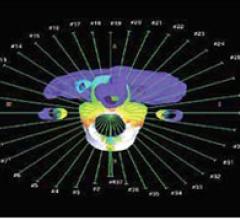

June 23, 2011 — Cancer patients in the United Kingdom will soon have access to two of the world's most advanced radiotherapy treatment machines.

June 21, 2011 – In just four years, Clinique Claude Bernard's Private Radiotherapy Center (PRCM, Metz, France) will have doubled the number of patients receiving radiation therapy treatments per year – from 1,100 to a predicted 2,200 patients by the end of this year. This achievement was enabled by equipping first one, then all three of its Elekta Synergy treatment systems with Elekta VMAT (volumetric modulated arc therapy). With VMAT, single or multiple radiation beams sweep in arc(s) around the patient, which can significantly reduce treatment times. On April 28, a patient with breast cancer became PRCM's 2,500th to receive VMAT since the clinic began using the technique in 2009.